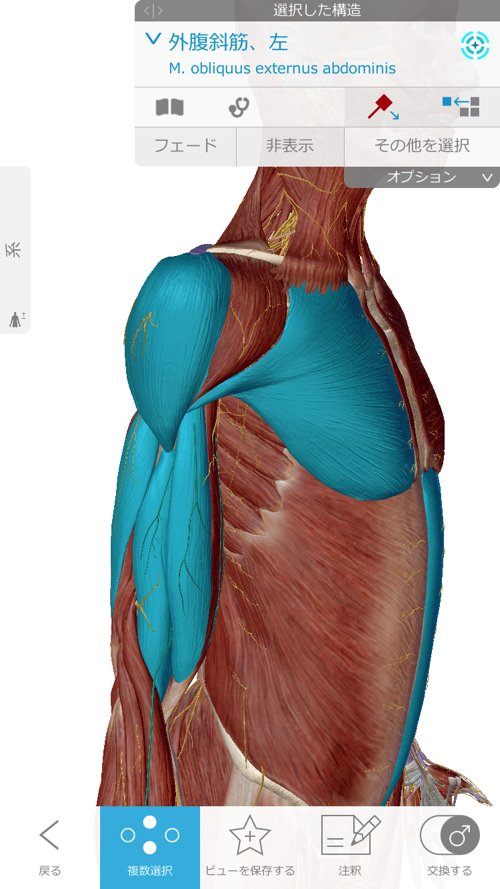

顎下から鎖骨、そして肘に向かうラインに硬直やヨジレが集中しています。

そして首の後ろ側は脇の辺りまで硬直。

そして胸周りから上腕をしっかり調整。

次に顎周りを緩めて首周りの硬直とズレをなくします。

そして四十肩に大きく関連している鎖骨周りを調整。